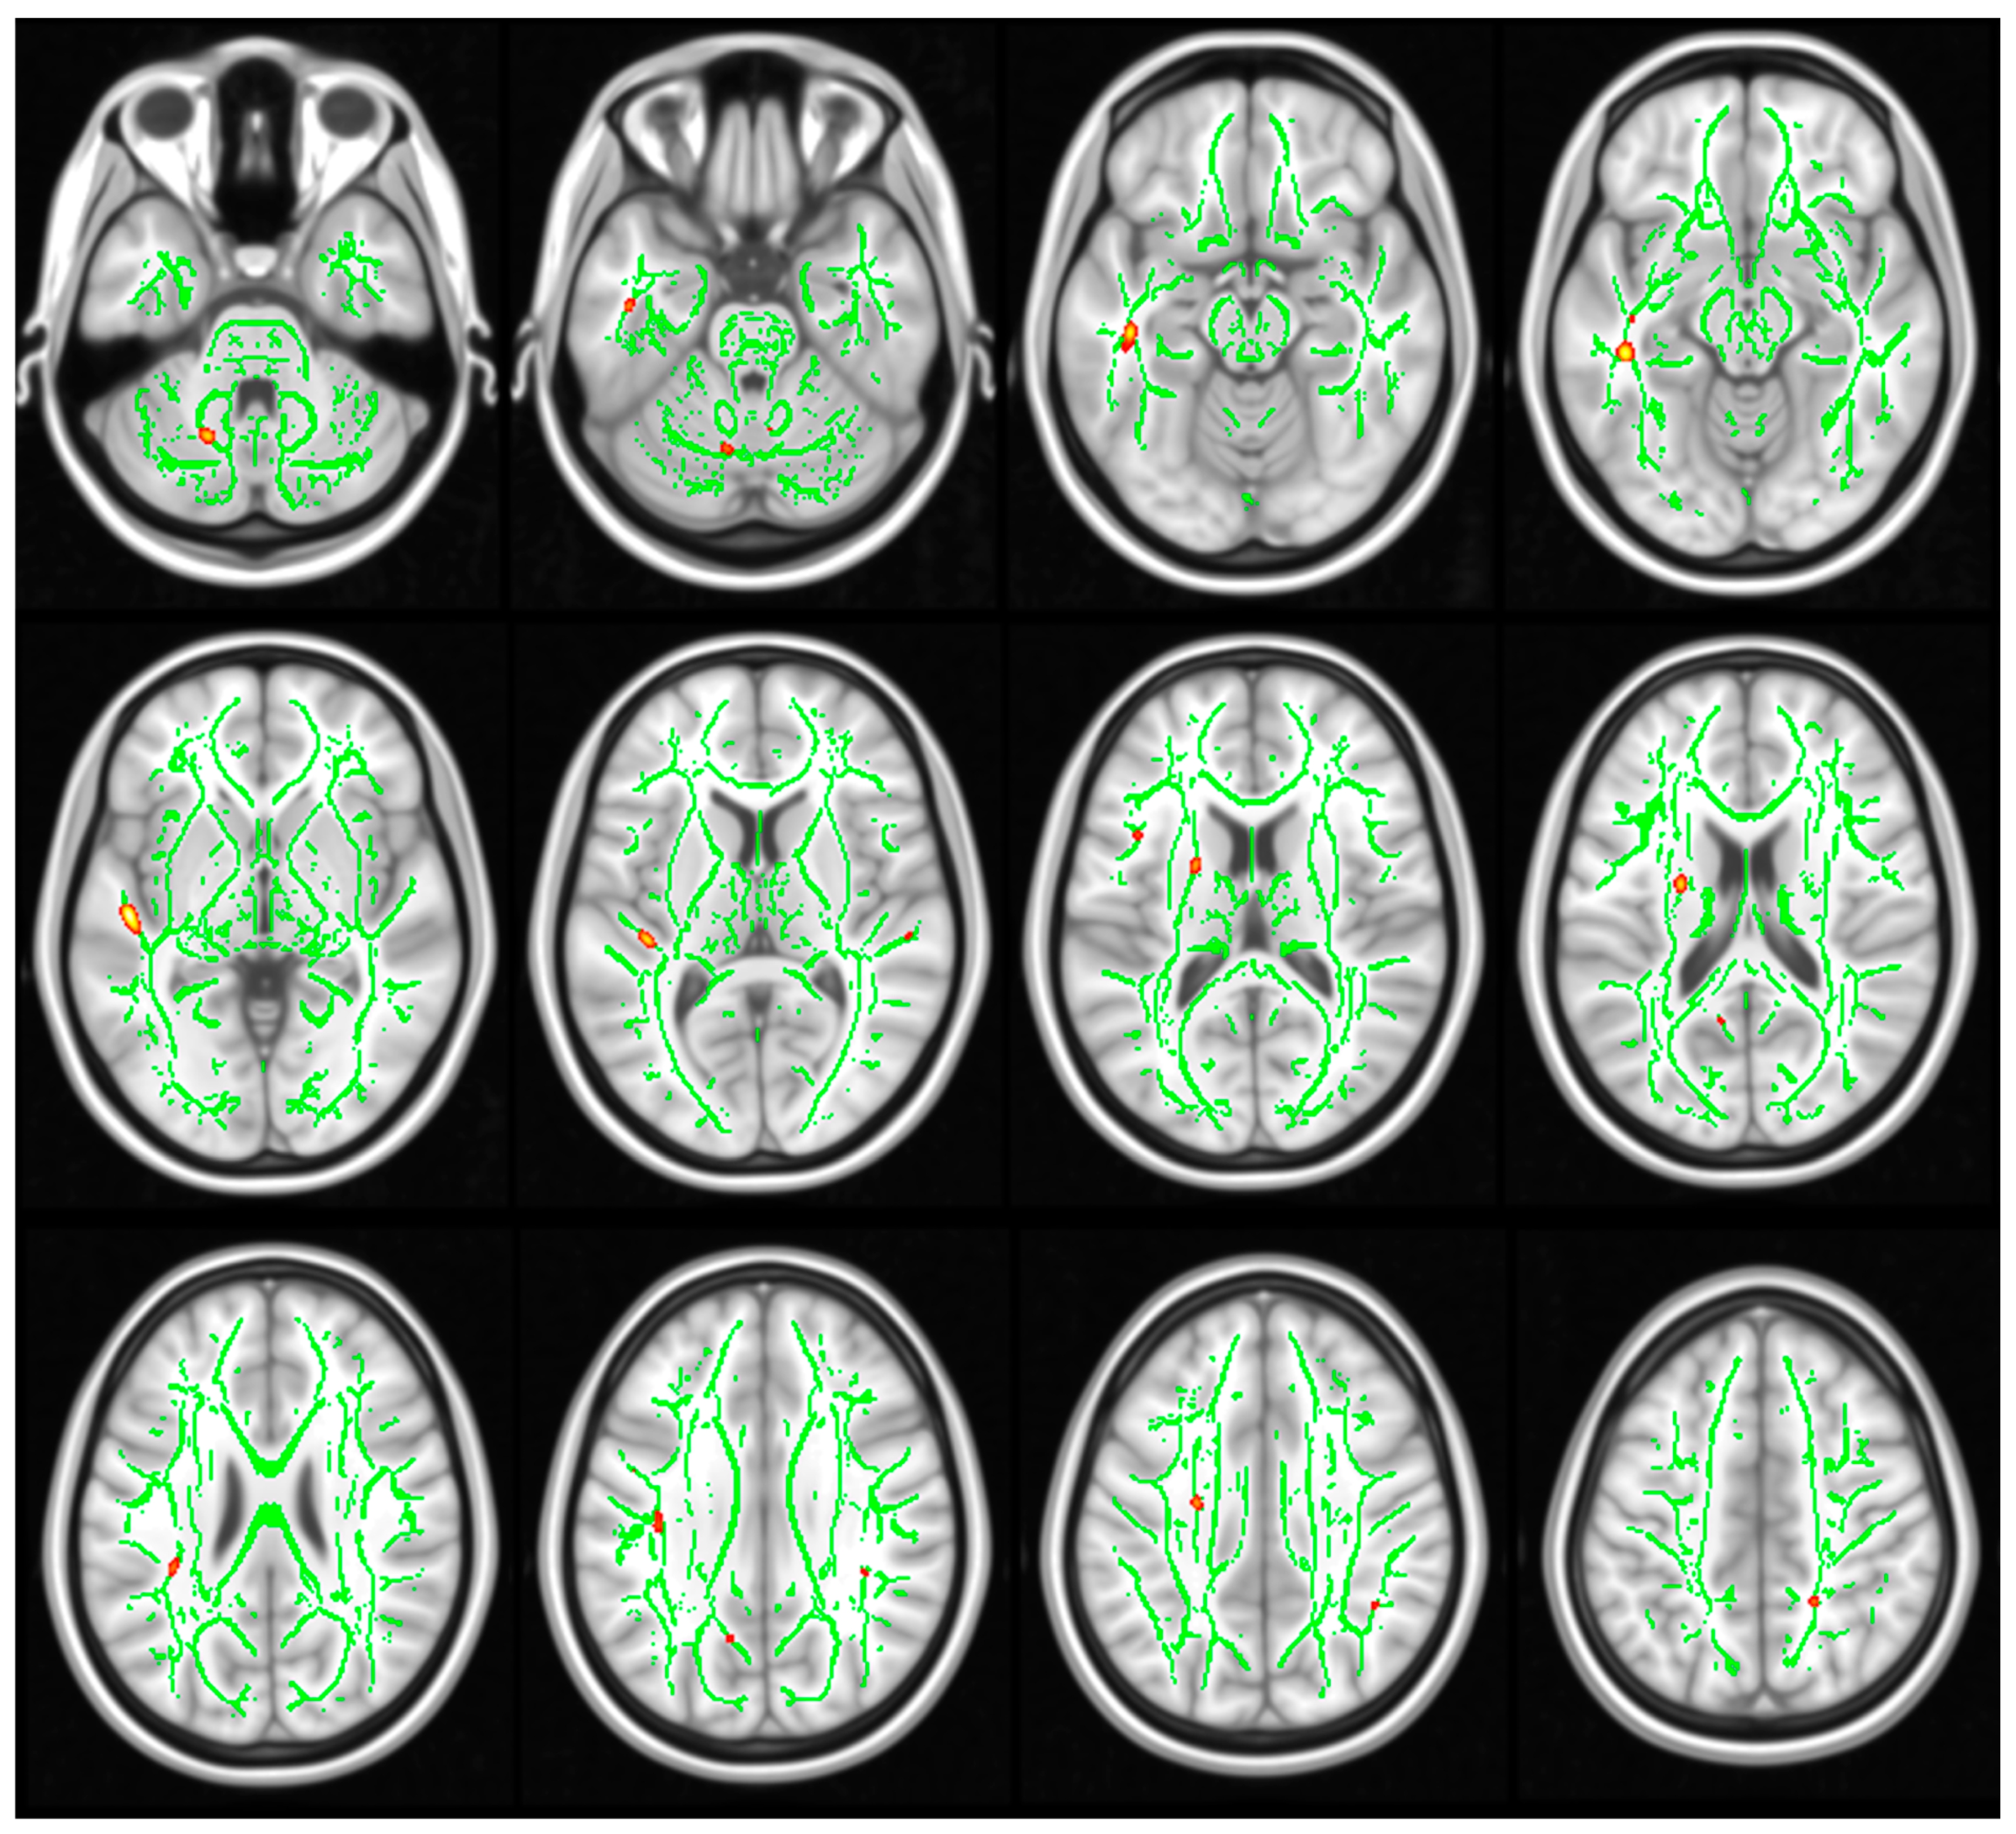

3.3. DTI Results

2.3.3. Statistical Analysis